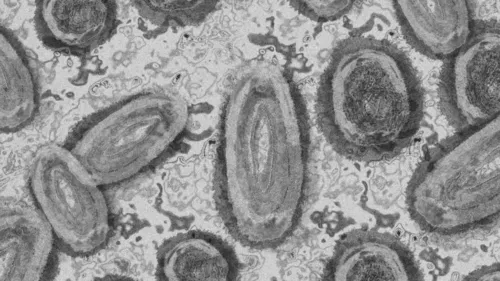

Autor A varíola dos macacos é uma doença viral rara transmitida pelo contato próximo com uma pessoa infectada e com lesões de pele - Foto: Pixabay

A varíola dos macacos, em inglês, monkeypox, é uma doença viral rara transmitida pelo contato próximo com uma pessoa infectada e com lesões de pele. O contato pode ser por abraço, beijo, massagens ou relações sexuais. A doença também é transmitida por secreções respiratórias.